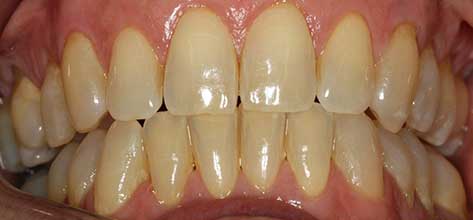

Blanqueamiento

Dra. Carmen Feito Bárcena

El paciente vino con una sonrisa con coloración más apagada y manchas. Tras el tratamiento con un blanqueamiento dental, se muestra una clara mejoría en luminosidad, con un aspecto homogéneo.